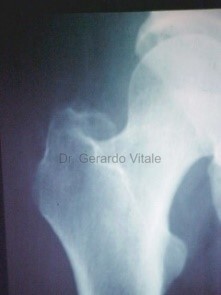

Diagnóstico:

El diagnóstico se basa en la presentación clínica, antecedentes del paciente, etc.

Estudios médicos que se pueden solicitar según el caso clínico son; Análisis de sangre (recuento de glóbulos blancos, marcadores inflamatorios etc.) Radiografías, Ecografía y la Resonancia Magnética pueden ayudar a distinguir las causas infecciosas de las no infecciosas.